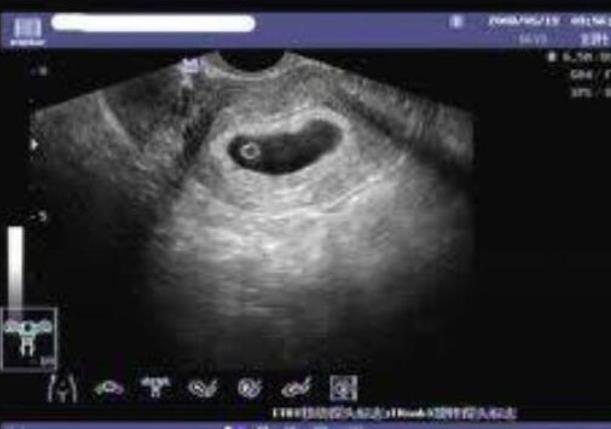

大家在选择做试管婴儿这项手术的时候,要综合各个情况来进行有效的分析,其实第一代试管婴儿技术相对来说都是非常不错的,我们要做好体外的肾经以及胚胎的移植,而且这也是最常见的技术,针对于女性患者存在输卵管堵塞或者是子宫内膜异位症,还有排卵障碍所导致的不孕不育的问题同样也很重要,那么这样的一项技术就是把男性取出的精子和女性的卵子在体外进行筛选的一个过程。

第二代试管婴儿技术同样也很重要,我们在选择第二代试管婴儿技术的时候,要结合具体情况来进行了解,这种单精子注射技术,是和男方患有严重的少精症,弱精症的患者,同时针对于严重畸形的精子的患者也可以做治疗,这样的一项技术是把男性的精子全部都提取出来,在体外经过胚胎实验由专家进行筛选,这样的话获得活动能力相对较好,或者是形态正常的精子。

当我们要选择做试管婴儿这项手术的时候,大家要选择第三代试管婴儿技术,这样的一项技术针对的都是担心的遗传病或者是染色体遗传病的遗传问题的患者,这一项技术就是通过第一代试管婴儿技术或者是第二代试管婴儿技术取得可用胚胎之后,然后在胚胎移植之前对于早期的胚胎进行遗传学的筛查,这样的话就能够挑选整个染色体正常的胚胎进入到女性的宫腔中。